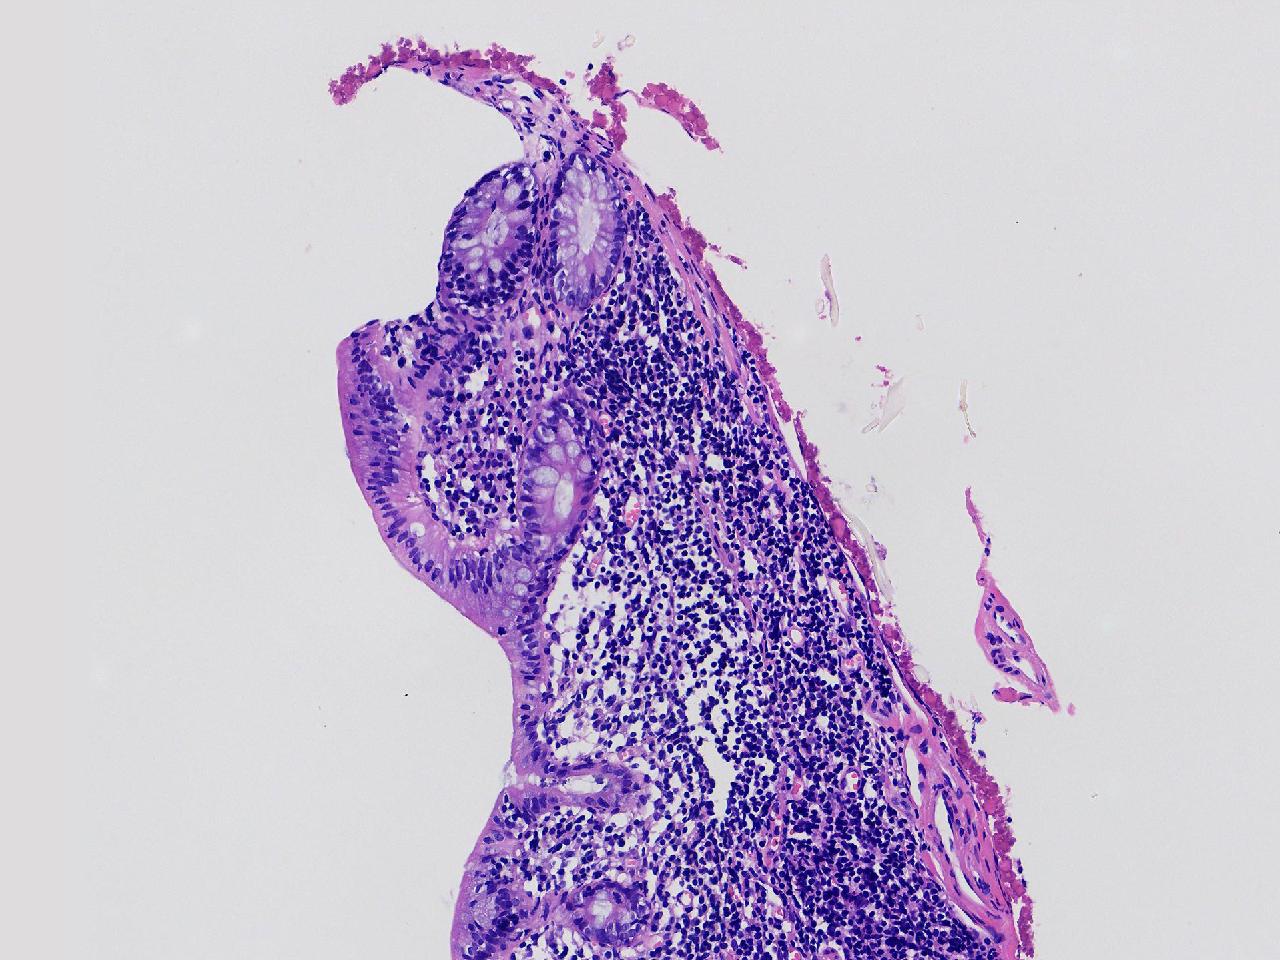

可见淋巴组织增生? 炎性?

性别

女

年龄

75岁

临床诊断

肠镜活检

一般病史

升结肠.降结肠.乙状结肠.直肠见多发直径约0.2—0.3厘米大小不等的扁平及指状隆起,表面光滑,升结肠取材1块。

标本名称

乙状结肠处活检

大体所见

灰白色不整形软组织1块。

粘膜慢性炎,局部淋巴组织增生。